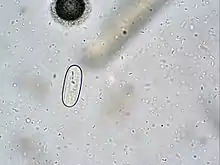

| Spirocerca lupi egg. | |

Faecal evaluation is readily available and in some hands, especially those using the sugar flotation technique of Markovics24, (as opposed to standard Zinc-Flotation techniques), diagnostic accuracy is very high (80% sensitivity). Most practices do not have this sugar solution or understand the technique and thus faecal flotation is not very sensitive. The Spirocerca eggs are light and small, and easily missed.